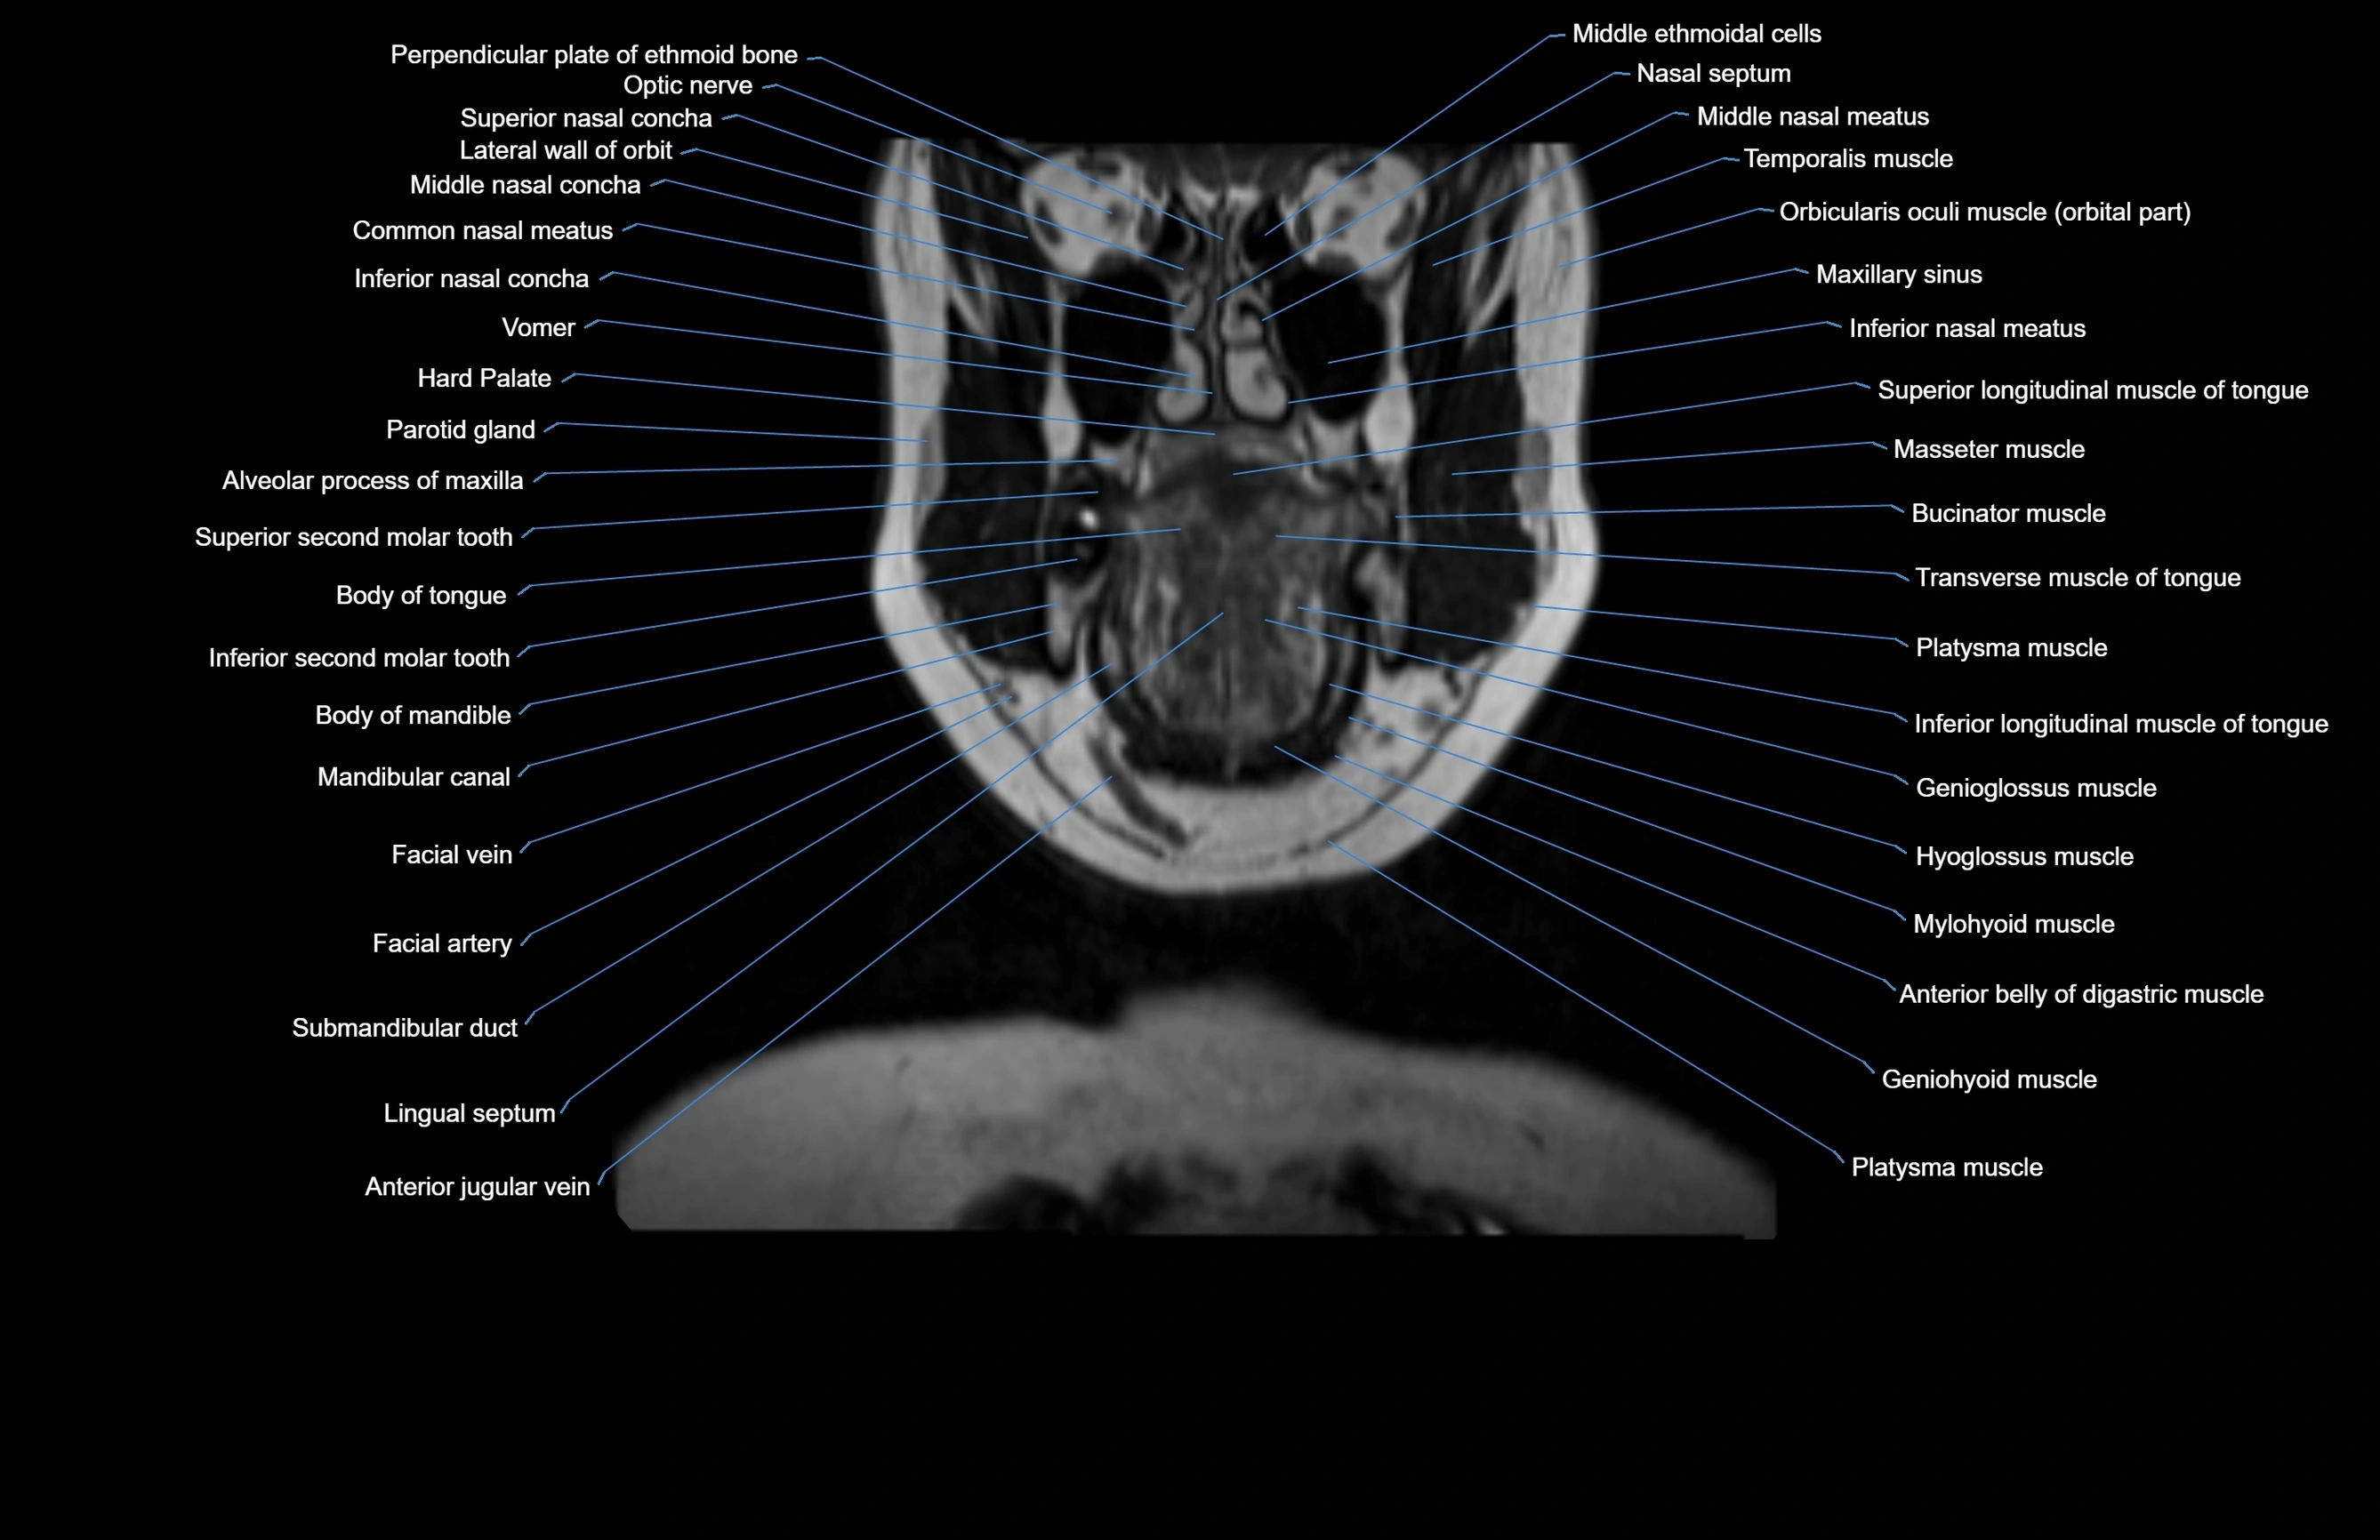

MRI images